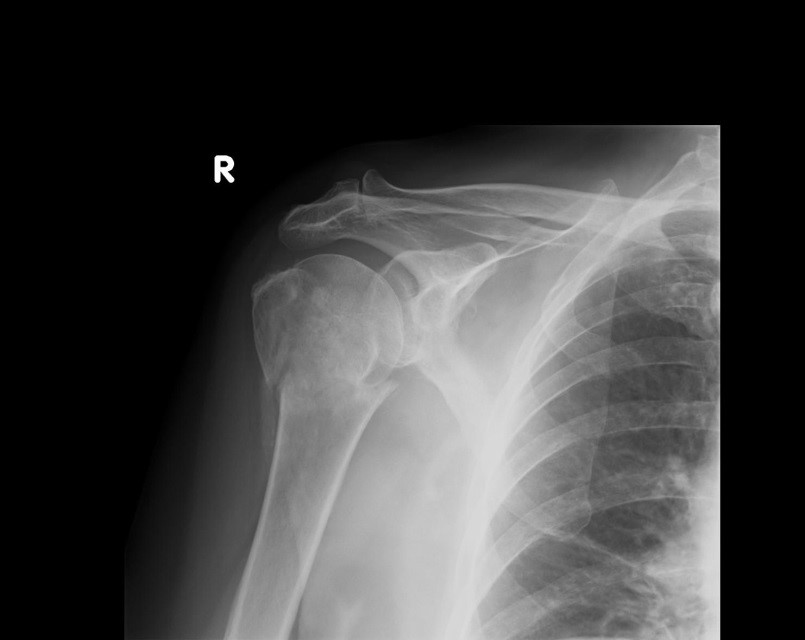

Na radiogramie uwidoczniono złamanie

A. obojczyka.

B. kości ramiennej.

C. wyrostka barkowego.

D. wyrostka kruczego.